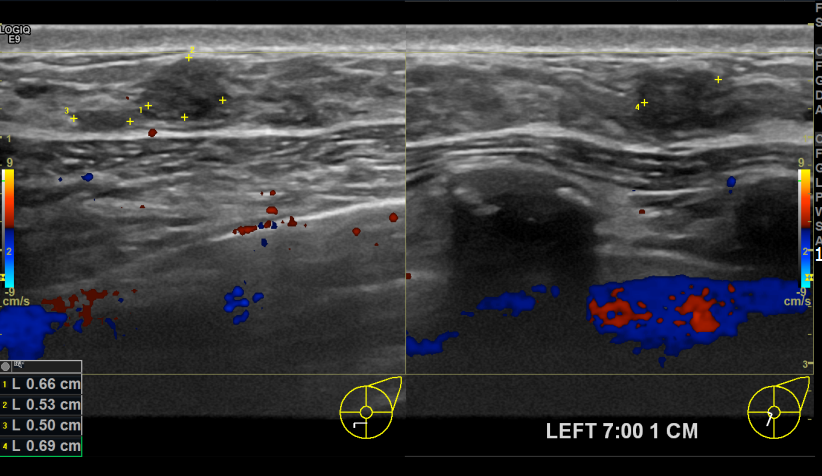

아산유외과개원후 759번째 유방암진단

상기환자 외부검진상 이상소견으로 내원하신 40대여성분으로 좌측유방에 의심스러운 혹 조직검사 후 유방암 진단되셨습니다.